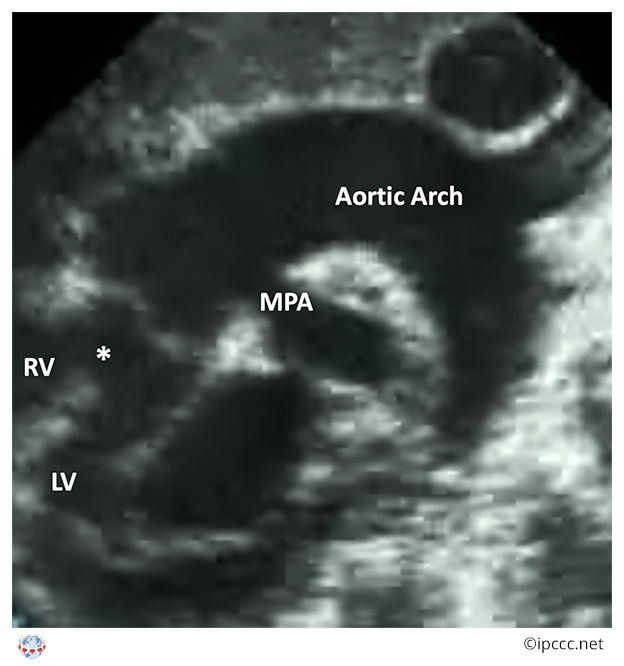

A congenital cardiovascular malformation in which a common arterial trunk is associated with an unobstructed aortic arch and both pulmonary arteries arise from the common arterial trunk.

This category includes Collett and Edwards truncus arteriosus types I, II, III and Van Praagh truncus arteriosus types 1, 2.

Echocardiogram